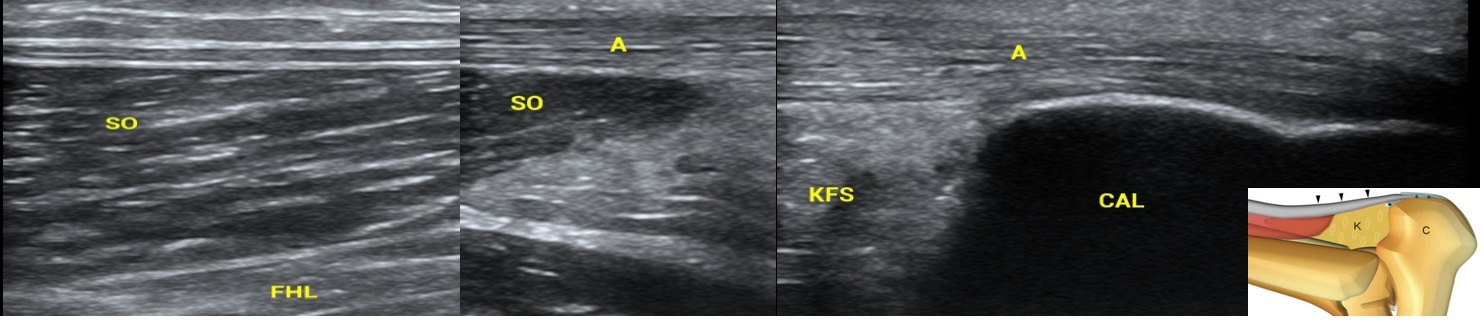

图3 跟腱超声长轴(上图),短轴(下图)超声自肌-腱结合部开始至跟骨附着